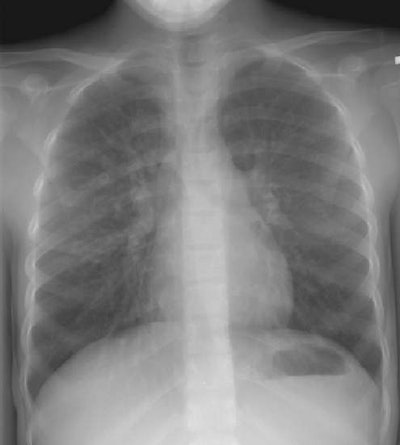

The CXR demonstrates the characteristic findings of cystic fibrosis with predominantly upper lobe involvement. A ring shadow indicative of bronchiectasis can be seen in the right upper lung.